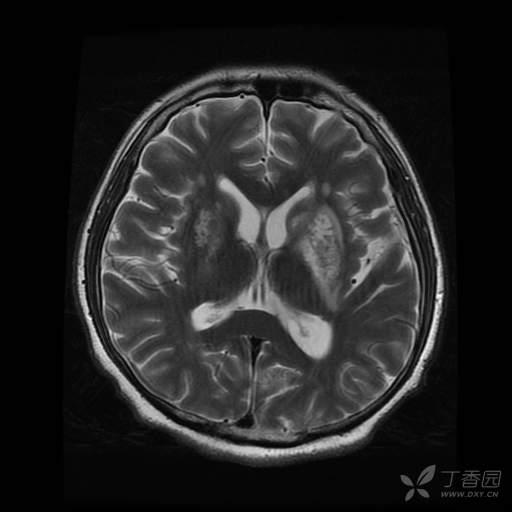

病人入院时意识清,对答如流,入院第 2 天心跳骤停抢救成功后出现言语减少。入院 33 天完善颅脑 MRI ,提示双侧基底节区及放射冠区异常信号;脑白质变性,脑内多发脱髓鞘灶;双侧小脑半球萎缩;右侧上颌窦囊肿。

导致患者意识状态改变的原因是什么?从这份头颅 MRI 能得出什么诊断?